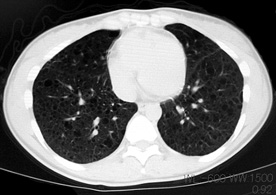

LAM患者さんに認められた両側肺気腫(右図:胸部CT)

初診時CT(左)から2年後のCTでは肺の嚢胞化が著明となっている。